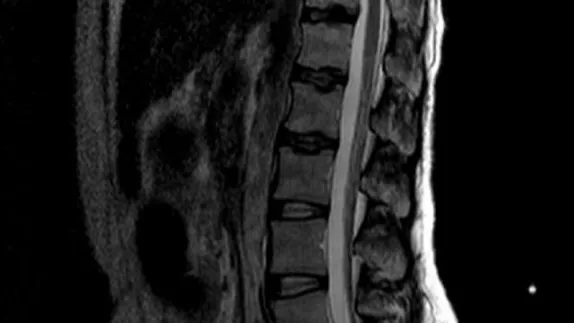

Пациентка была консультирована нейрохирургом МОНИКИ, и первоначально было принято решение о необходимости оперативного вмешательства, сообщили в пресс-службе Каширской больницы. Однако в ходе дополнительных обследований была выявлена анемия средней тяжести и эрозивный гастрит, усложнившиеся из-за неконтролируемого приема обезболивающих препаратов. Это вынудило врачей отложить операцию и пересмотреть план лечения.

Вместо операции пациентке была проведена паравертебральная анестезия поясничной области. Этот метод предполагает введение анестетика в область вокруг позвонков, что приводит к временному блокированию передачи нервных импульсов от позвоночника к мозгу, и значительно снижает болевой синдром. Такая процедура позволила пациентке вновь обрести возможность ходить, после она была переведена в терапевтическое отделение для дальнейшего лечения и восстановления.